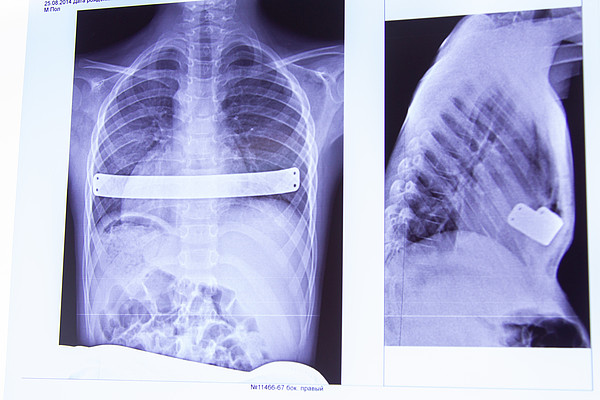

IMG_1741.